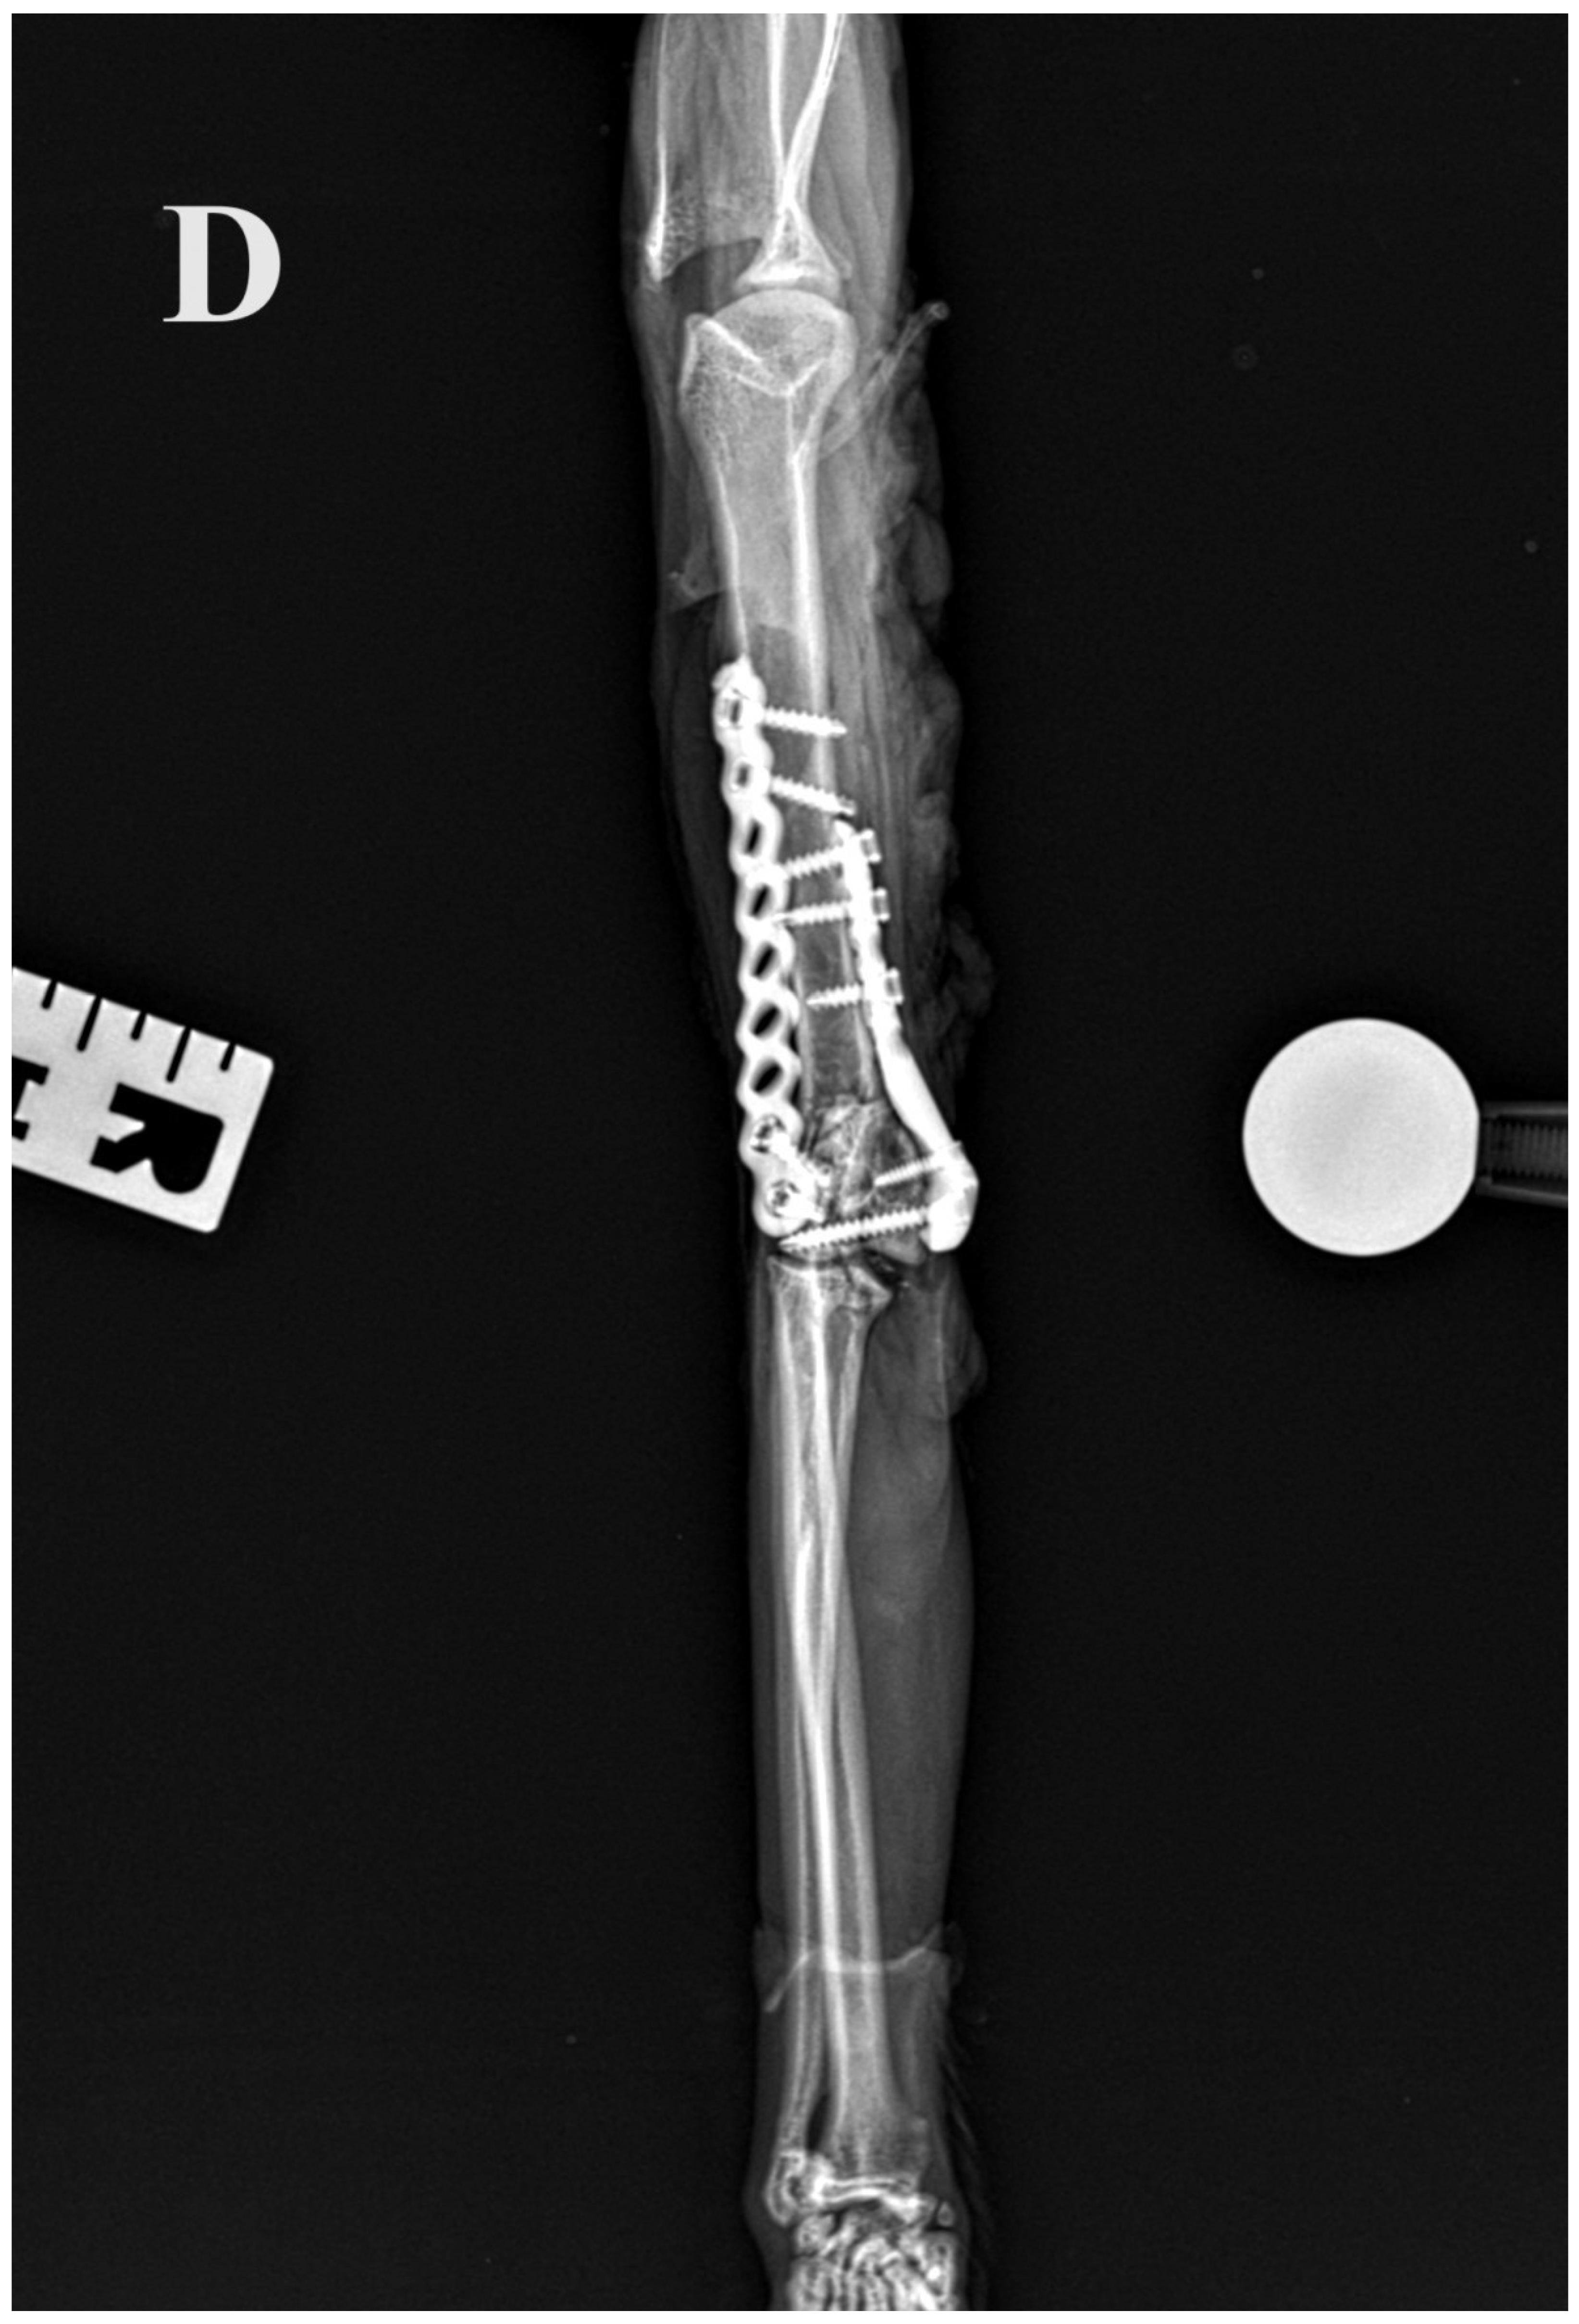

Figure 5.

(A,B) Initial lateral and cranio–caudal radiographs of the right forelimb of a female domestic cat show a displaced Y-T fracture. (C,D) Postoperative lateral and cranio–caudal radiographs show a small articular surface defect (<1 mm) of humeral condyle and adequate alignment, adjacency and apparatus (2.0/2.4/2.7 3D printed plate, 2.4/2.7 straight interlocking bone plate and screws).